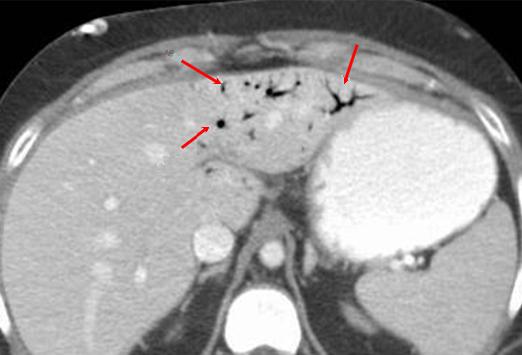

La presence de

gas au systeme portal intra hepatique dans colite

ischemique . Inmage radiologique TDM en coupe axiale |